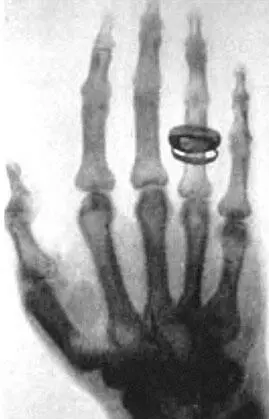

Это один из первых снимков, сделанных самим Рентгеном.

Рука сфотографированная лучами Рентгена Это тоже один из первых снимков - фото 35

Рука, сфотографированная лучами Рентгена

Это тоже один из первых снимков, сделанных Рентгеном. Рука на фотографии – жены Рентгена. Видно кольцо, надетое на палец.